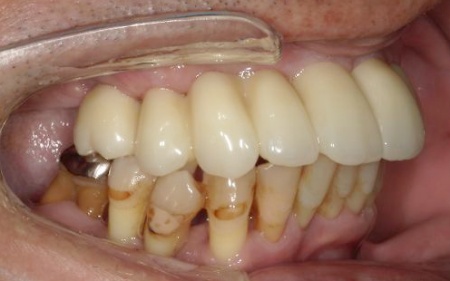

拝見したところ、患者様は上前歯が数本欠損しており、残っている歯を利用して橋渡しのように歯を補うブリッジ治療が行われていました。しかし、転倒による衝撃でブリッジが外れていました。

また、患者様は重度の歯周病によって歯を支える骨が減少し全体的に歯が揺れていました。

残っている上の歯7本(左右上側切歯、左右上犬歯、左右上第1小臼歯、左上第1大臼歯)と右下奥歯2本(第2大臼歯、第3大臼歯)は残すことが難しく抜歯が必要な状態です。